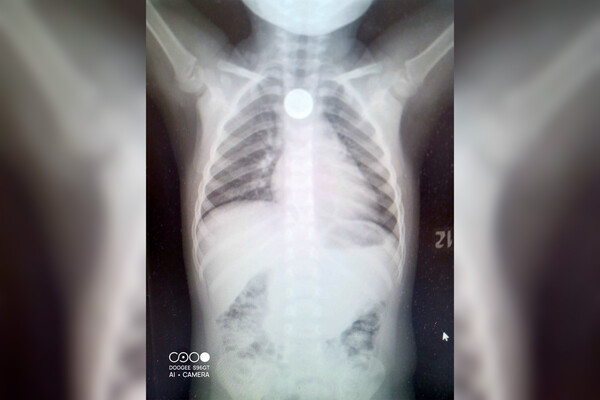

Хирурги осмотрели мальчика и приняли решение срочно направить его на рентген. В пищеводе ребенка обнаружили инородное тело — это была монета, которая застряла в одном из физиологических сужений.

Мальчика доставили в кабинет эндоскопии. Врачи экстренно удалили инородное тело из пищевода ребенка — это оказалась монета номиналом в один рубль.